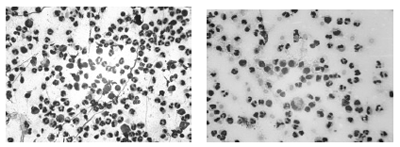

Как видно из диаграммы 1, на 4-ые сутки в экссудате из ран имеется повышение количества полиморфноядерных нейтрофилов и их дегенеративных форм, тогда как количество лимфоцитов снижается незначительно. На фотографиях цитограмм 2-го и 4-го дня отчетливо видна указанная динамика клеточных изменений (рис.1,2).

рис.1. Контрольная группа, 2-ой день |

рис.2. Контрольная группа, 4-ой день |

В цитограммах большинства больных, получив-ших ЛТ, выявлено снижение количества полиморфноядерных нейтрофилов и их дегенеративных форм с заметным повышением количества лимфоцитов к 4-ому дню. На фотографиях цитограмм отображены наиболее характерные изменения клеточного состава при адекватных дозах лазеротерапии на 2-ой и 4-ый день (рис 3,4).

рис.3. Адекватная ЛТ, 2-ой день

рис.4. Адекватная ЛТ, 4ый день